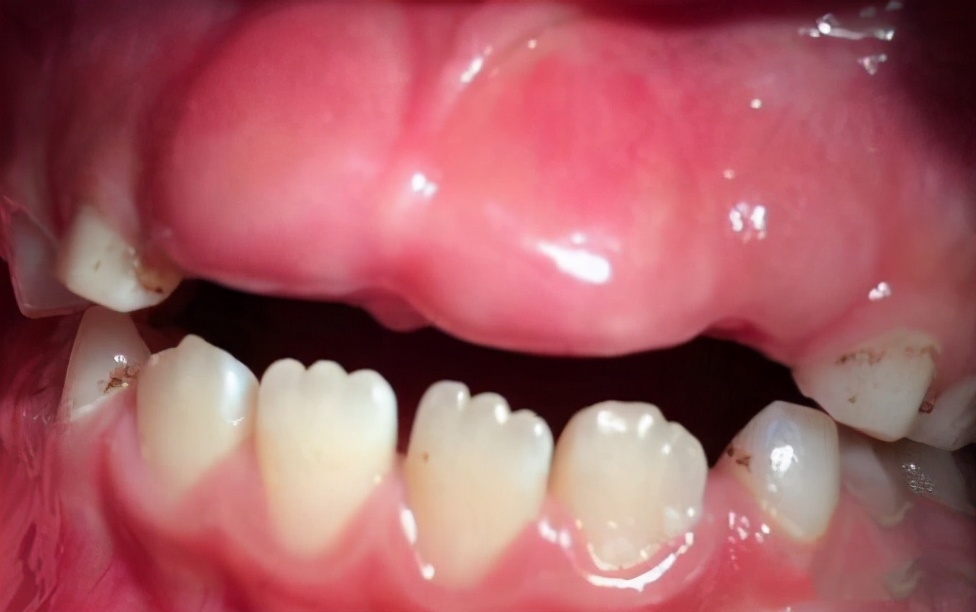

2、牙龈增厚

这是因为乳牙过早脱落,导致牙龈长期受到咀嚼摩擦而变厚变硬,这就是牙龈增厚。打个比方,本来欣欣的乳门牙要在7岁时自然掉落,但是在她6岁的时候因为摔跤意外把门乳牙磕掉了,而正常恒门牙需要到7岁才能萌出,那么在这一年时间里,欣欣长门牙的地方就会一直空着,吃东西咀嚼会摩擦裸露的牙龈导致其变厚。等到恒门牙要长出来的时候,因牙龈太厚太硬就难以长出,这时就需要切开增厚的牙龈,帮助新牙长出,这就叫微创开窗助萌术。